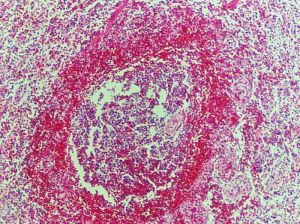

小兒丹毒丹毒相當於西醫的急性網狀淋巴管炎。其特點是:患處皮膚突然鮮紅成片,色如塗丹,灼熱腫脹,迅速蔓延,伴有惡寒發熱、頭痛等全身症狀,每多復發,下肢復發性丹毒可形成象皮腿。應與發、接觸性皮炎相鑑別。風熱毒蘊證,治宜散風清熱解毒.方用普濟消毒飲加減;濕熱毒蘊證,治宜清熱利濕解毒,方用五神湯合萆蘚滲濕湯加減;胎火蘊毒證,治宜涼血清熱解毒,方用犀角地黃湯合黃連解毒湯加減。

丹毒好發於下肢及頭面部,炎症呈片狀紅疹,色鮮紅似玫瑰,界限清楚,用手指輕壓,紅色即可消退,除去壓力時紅色很快恢復,紅腫向四周蔓延,有時可發生水皰,往往邊緣高出正常皮膚,病人可伴有高燒39℃~40℃,頭痛,畏寒,大便乾燥等全身症狀。丹毒可反覆發作,後期可造成象皮腫,全身治療用大劑量青黴素G或磺胺,局部治療用50%硫酸鎂或4%硼酸溶液濕敷,中藥外敷或外洗治療。治療期間應注意抬高患肢,臥床休息。